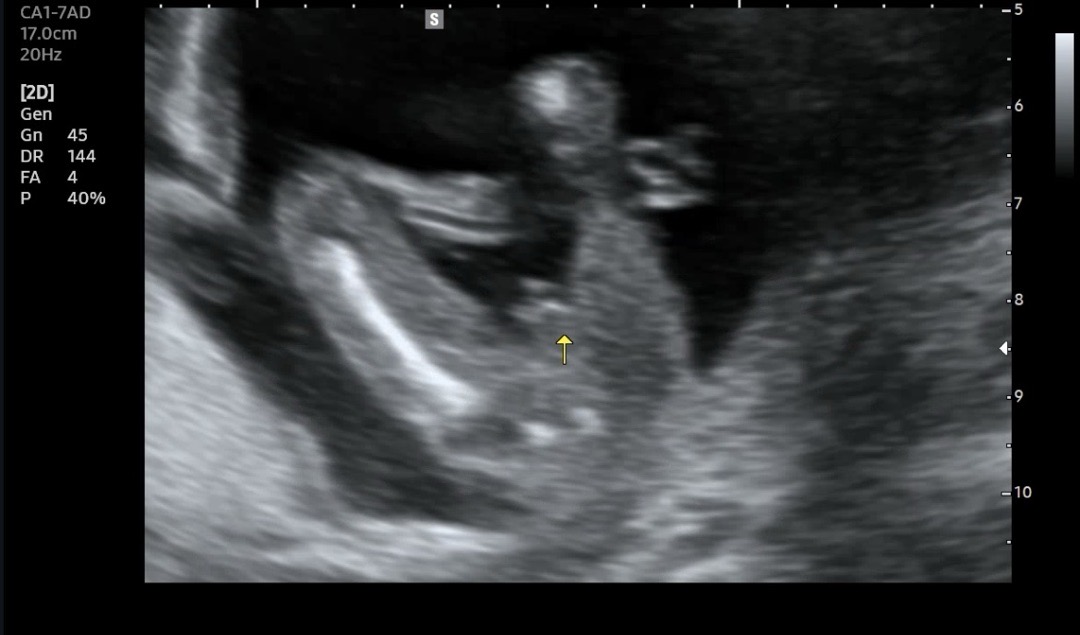

이제 17주 접어들어요 오늘 성별보러갔는데 아기가 다리를 안벌려서 한참 못보다가 마지막에 잠깐 보여줬는데 아들 같나요..? 선생님도 확답은 못드리는데 80%아들이라 하시는데 이랬던 분들 계신가요??? 탯줄이 지나가고 있어서 애매하대요 ㅎㅎ..

초음파사진은 아들인데...ㅎㅎ

저도 다시보니까 아들같아요...😅😅